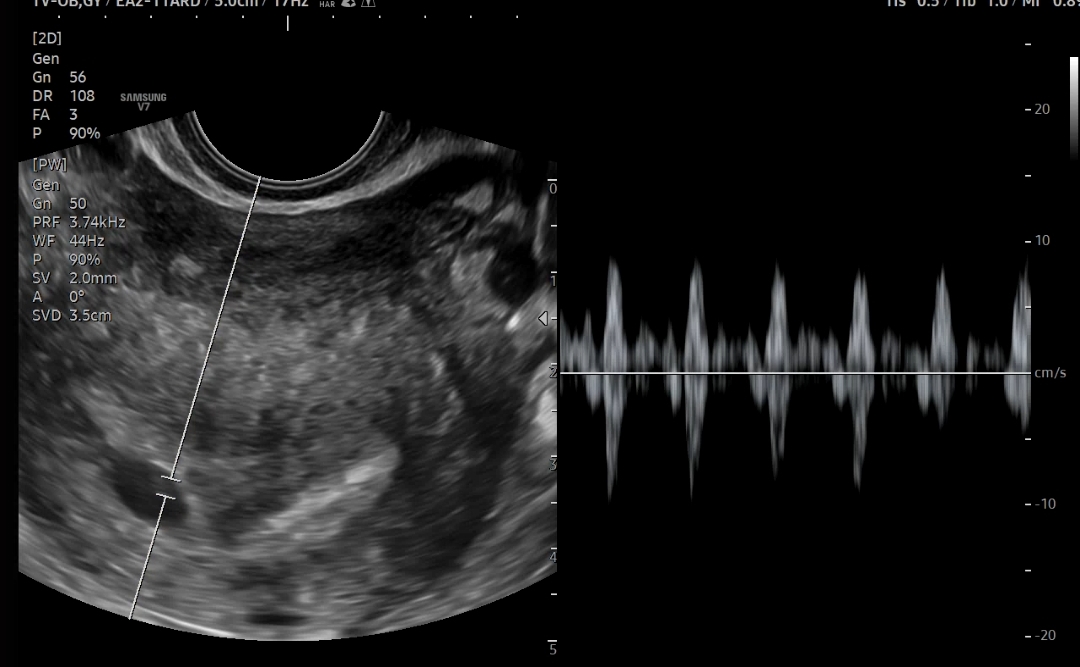

📍심장박동은 111bpm이 찍혔다.

6주에 100-120 사이면 정상 수치라고 하셨다

이번임신에서 처음 듣는 심장소리지만 감격스럽거나 그런건 없었다. 그냥 계속 조마조마.. 한 관문 넘었구나 생각이 들었다 계류유산 경험이 있어서 그런가 ...

무근 심장박동 소리도 들었지만